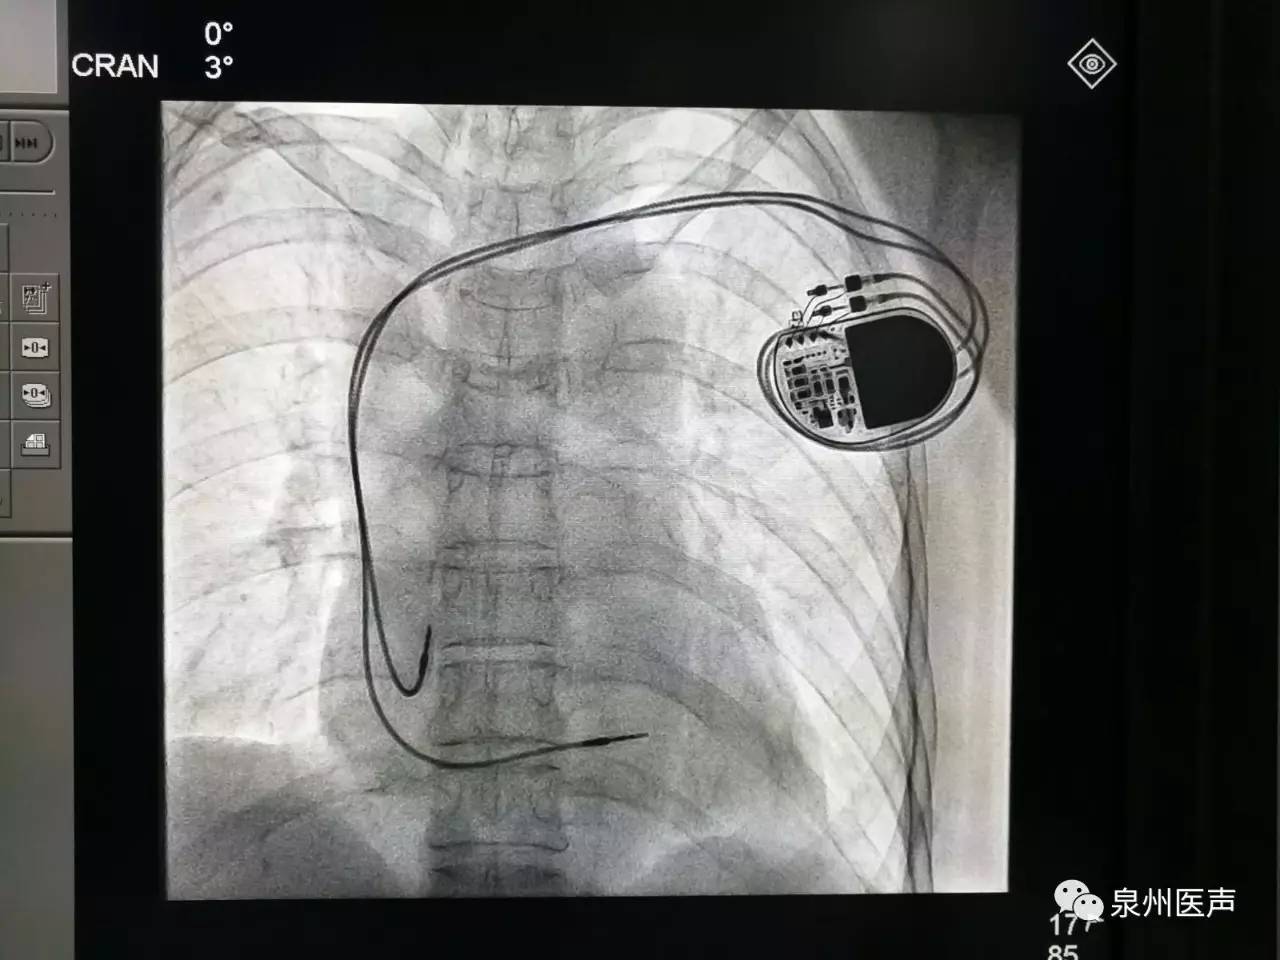

全球唯一!無線雙腔起搏器首次植入

來源:器械之家,未經(jīng)授權(quán)不得以任何形式轉(zhuǎn)載,且24小時(shí)后方可轉(zhuǎn)載。2022年2月7日雅培宣布,其在研型Aveir?雙腔無引線起搏器完成了全球首例患者植入,這也是全世界第一個(gè)雙腔無線起搏器。Aveir?DR雙腔起搏器提供右心房和心臟右心室的同步、逐次跳起搏,近80%接受起搏器治療的患者需要雙腔選擇,A